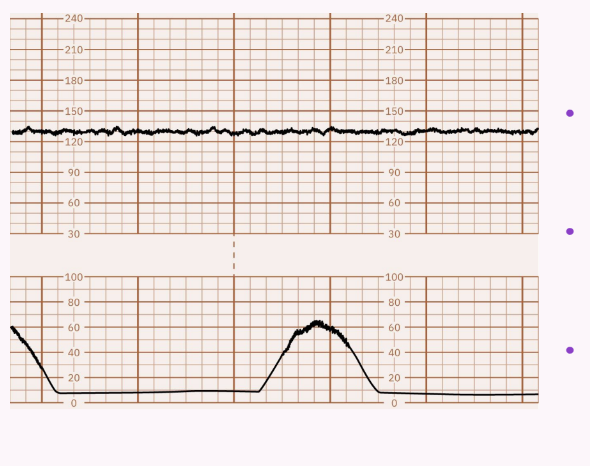

Absent: Undetectable; associated with risk for fetal metabolic acidemia, requires prompt evaluation.

Absent Variability: No detectable changes in fetal heart rate; typically associated with fetal distress and requires immediate evaluation. NEVER WANT TO SEE STRAIGHT LINES!!!!!